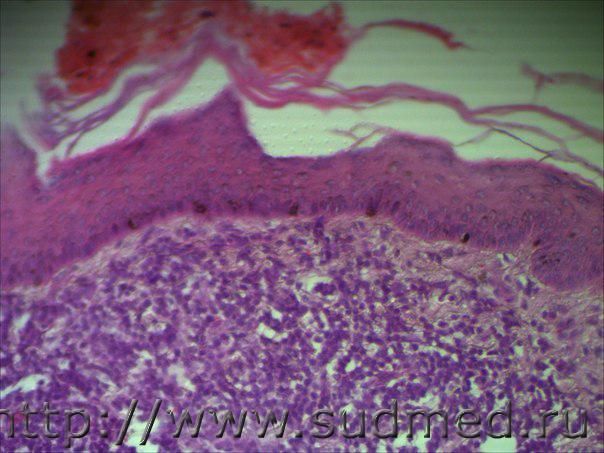

Н/О в области соска у кабеля

Я бы сказала.что это зло. Аденокарцинома вероятнее всего. Поточнее могу завтра, атласы на работе.

Остановился бы на недифференцированном раке.

Опухоль из элементов потовой железы. На фото 7 наблюдается апокринный тип секреции. В 1 и 8 фото видны мелкие участки гиалиноза.

Гиалиноз - тяжелый тип дистрофии(сосудисто-мезенхимальной). А зло - это при наличии атипии клеток или эпителии, неважно какого генеза с активным патологическим митозом ядер и полиморфизмом клеток с безудержным размножением и изменением биохимических свойств разрушающих нормальную структуру в ткани или целого органа. В данной ситуации не исключается зло, но пограничный период м.б. Нам несовсем виднее, чем Вам т.к. материал только у Вас.